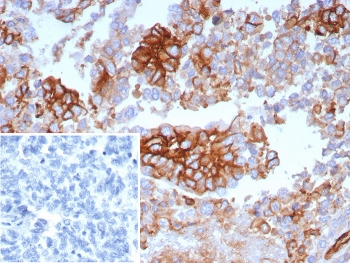

IHC staining of FFPE human ovarian carcinoma tissue with SLC2A1 antibody (clone GLUT1/7308). Inset: PBS used in place of primary Ab (secondary Ab negative control). HIER: boil tissue sections in pH9 10 mM Tris with 1 mM EDTA for 20 min and allow to cool before testing.